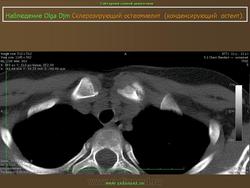

Синонимы - Stieda (Штида) (Штиды) - Albers-Schonberg (Альберс-Шенберга) болезнь - Кость пятнистая - Остеопатия врожденная пятнистая множественная - Остеопатия врожденная рассеянная склерозирующая - Остеопатия диссеминированная конденсирующая - Остеопойкилия - Остеопойкилоз - Штиды (Штида) (Stieda) - Альберс-Шенберга (Albers-Schonberg) болезнь Характеристика Врожденное нарушение развития костей. Клинически не проявляется. Случайная рентгенологическая находка. Рентгенологическая картина Множественные мелкие и крупные (до 10 мм) очаги остеосклероза округлой или овальной формы, расположенные в эпифизах трубчатых костей, а также в других костях, за исключением ключицы.

Остит генерализованный конденсирующий

Характеристика

Врожденное нарушение развития костей. Клинически не проявляется. Случайная рентгенологическая находка.

Рентгенологическая картина

Множественные мелкие и крупные (до 10 мм) очаги остеосклероза округлой или овальной формы, расположенные в эпифизах трубчатых костей, а также в других костях, за исключением ключицы.